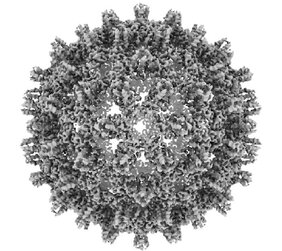

Nach Angaben der Weltgesundheitsorganisation (WHO) leiden mehr als 3% der Weltbevölkerung an einer chronischen Infektion mit dem Hepatitis-B-Virus (HBV), welche die Hauptursache für Leberzirrhose und Leberkrebs ist. Die derzeitigen Behandlungen heilen die Infektion nur sehr selten aus. Therapeutische Impfstoffe (Impfstoffe, die das Immunsystem zur Heilung einer Krankheit anregen sollen) stellen einen vielversprechenden Ansatz zur Behandlung einer chronischen Hepatitis B dar, haben aber in bisherigen Studien nur begrenzte klinische Wirksamkeit gezeigt. In den letzten zwei Jahrzehnten wurden zahlreiche Versuche unternommen, wirksame therapeutische Hepatitis-B-Impfstoffe zu entwickeln. Einige dieser Impfstoffkandidaten wurden in klinischen Studien getestet, aber keiner von ihnen hat bisher eine antivirale Wirkung bei Patienten mit einer chronischen Hepatitis-B-Patienten gezeigt. Daher ist es wichtig, die wesentlichen Faktoren zu identifizieren, die ausschlaggebend für eine erfolgreiche therapeutische Impfung sind und diese strategisch in das Impfstoffdesign zu integrieren.